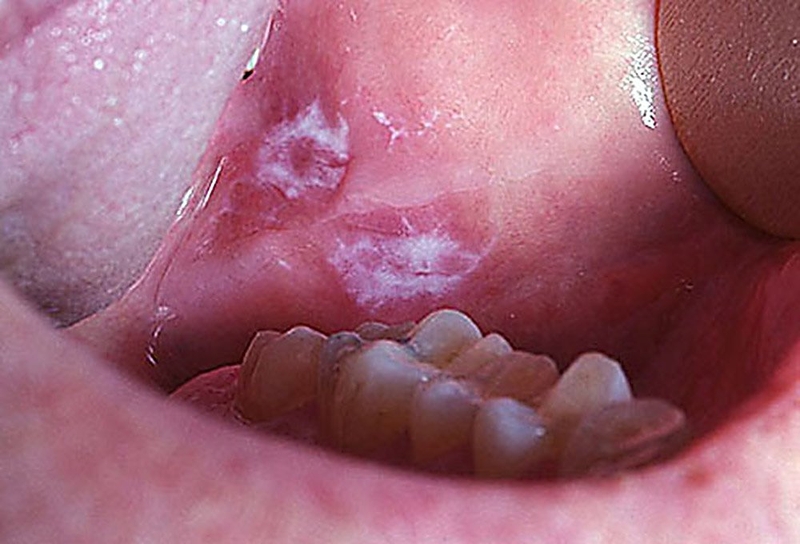

Ung thư lưỡi thường xuất phát từ các tế bào vảy lót trên bề mặt của lưỡi. Hai loại tổn thương được xác định là tiền thân của ung thư lưỡi là leukoplakia (tổn thương bạch sản) và erythroplakia (tổn thương hồng sản). Mặc dù leukoplakia phổ biến hơn, nhưng erythroplakia, với thành phần hồng cầu, có khả năng chuyển biến thành ung thư lớn hơn nhiều. Bất kỳ tổn thương nào không tự lành hoặc tự giảm trong vòng khoảng 2 tuần cần được đánh giá bởi bác sĩ có chuyên môn và có thể cần thực hiện sinh thiết để đặt chẩn đoán chính xác.